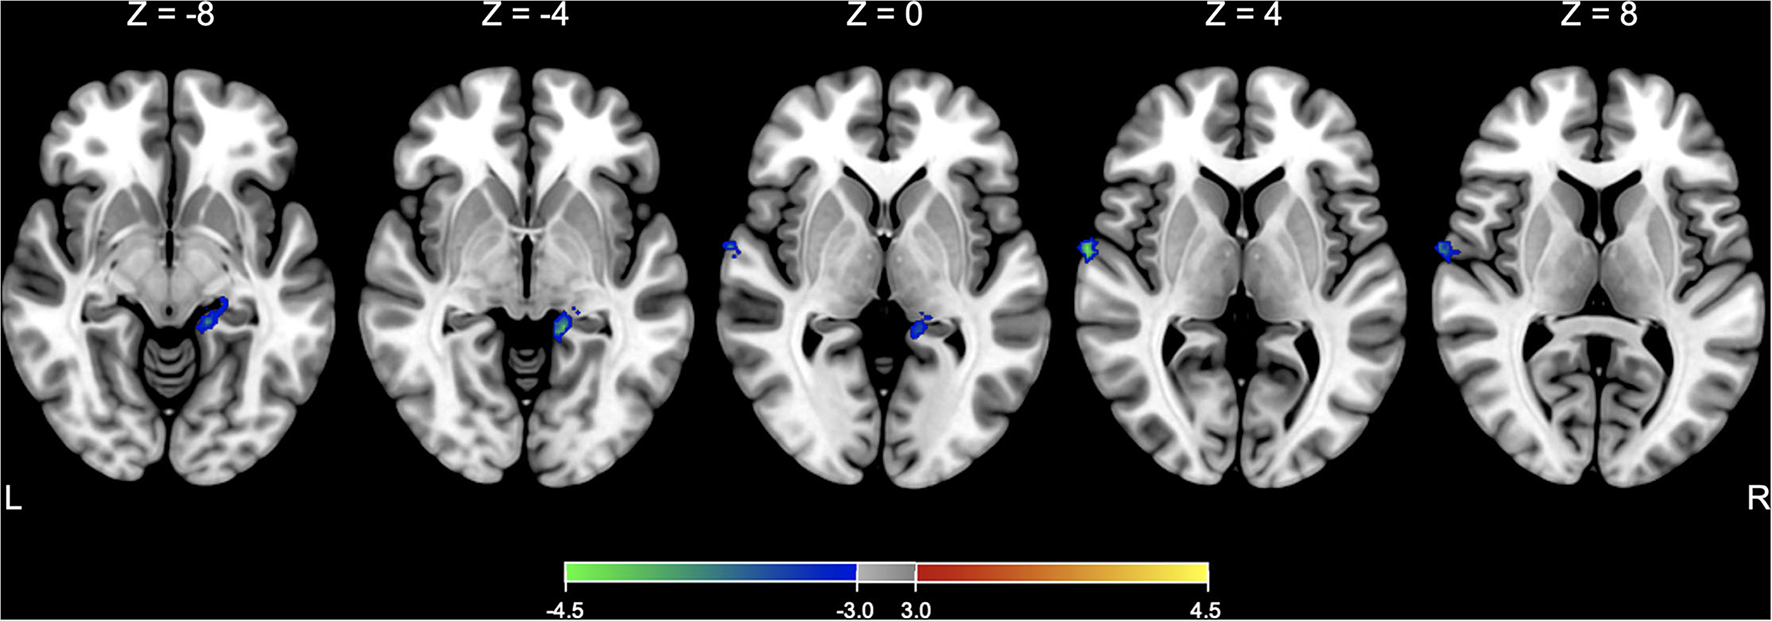

Before testing models of interest, a two-sample t-test model was conducted to compare the baseline SPECT images between the active and sham groups and found that there was no significant difference in rCBF between groups at the baseline. In comparison with the changes in rCBF between the groups, a flexible factorial model identified a significant treatment-by-time interaction effect in the right superior temporal gyrus and left hippocampus or parahippocampus, controlling for age and sex (Table 3 and Figure 3). Post hoc analysis of a paired t-test showed that the rCBF from the left superior frontal gyrus and left hippocampus was significantly decreased in the active group between the baseline and immediate follow-up, but no changes were observed in the sham group (Table 3).

Figure 3

SPECT analysis results. Significant areas with treatment (active vs. sham) x time (baseline vs. immediate follow-up) interaction effects of rCBF are overlaid on the Montreal Neurological Institute (MNI) 152 template. Color bar represents the voxel-level t-values.

In our study, the brain SPECT analysis revealed a significant treatment-by-time effect on rCBF in the left hippocampus and right superior temporal areas. The post hoc analysis showed that the rCBF was decreased at the immediate follow-up compared to the baseline only in the active group. Considering that these regions are regarded as the components of multimodal vestibular cortical areas (22), this tDCS protocol might have unintentionally exacerbated the maladapted brain function to the extent that clinical symptoms did not worsen.